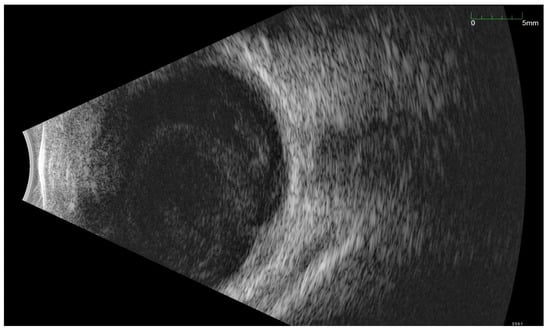

All of the above circumstances make the assessment of the vitreous body and retina in an ophthalmoscopic examination often impossible. The basic diagnostic tool in such cases is an ultrasound examination. Vitritis is inherent part of EE. Ultrasonography is nonspecific, however, it can indicate severity of the posterior involvement (Figure 6 and Figure 7) [80]. It also allows the assessment of the progression of changes (Figure 8). Features characteristic for EE include strands and membranes with reduced mobility (Figure 9). Other common changes are retinal detachment and subretinal abscess (Figure 10).

Figure 10.

Ultrasound B scan with numerous hyperechoic densities in vitreous chamber. The blue arrow marks a detached retina. Hyperechoic masses are visible under the retina.